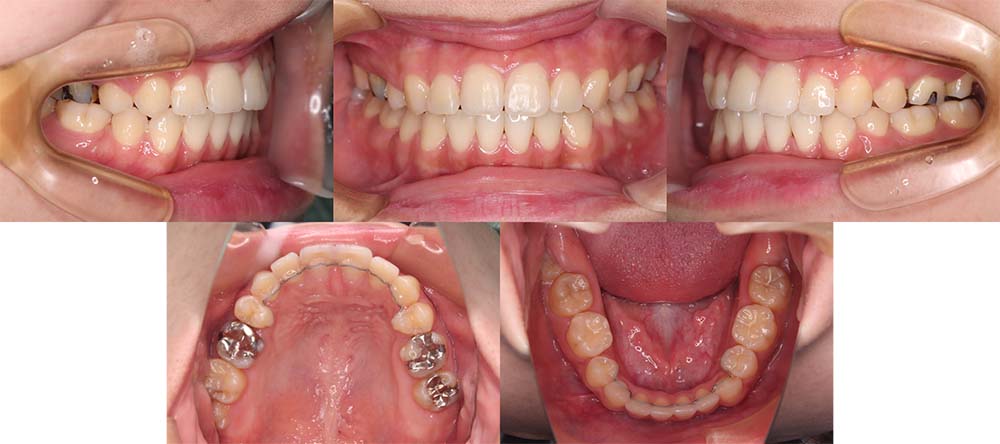

| 症例分類 | 叢生、上顎前突、口唇突出 |

| 診断名 | 下顎重度叢生を伴う骨格性上顎前突 |

| 主訴 | 歯並びが悪い、ものがよく噛めない、口元が気になる、歯科医師に勧められた |

| 年齢 | 22歳10ヶ月 |

| 性別 | 女性 |

| 抜歯部位 | 上下左右の第一小臼歯(4本) |

| 使用装置 | 表側のワイヤー装置 |

| 治療期間 | 2年2ヶ月 |

| 保定装置 | 固定式保定装置、取り外し式保定装置(8時間) |

| 費用 |

[検査・診断料] ¥49,500 [基本施術料] ¥792,000 [調整料] ¥4,400/回 [抜歯] ¥5,500/本 [保定装置] ¥55,000(税込) 抜歯や虫歯治療は他院にて費用が別途かかります。(抜歯¥4,000〜10,000/本)

下顎前歯重度叢生と上顎歯列の前方位、口唇閉鎖不全、口唇突出感があるため、上顎両側第一小臼歯と下顎両側第一小臼歯を抜去して治療を行いました。上顎前歯をしっかりと舌側移動しないといけなかったため矯正用アンカースクリューを使用しました。

前歯がしっかりと舌側移動できたため、口唇閉鎖不全が改善され口唇突出感もなくなり、問題なく咬合させることができました。